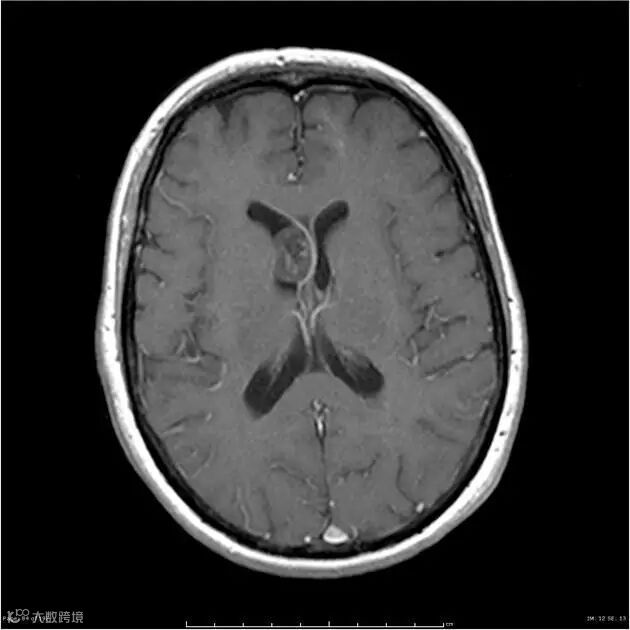

T1WI C+